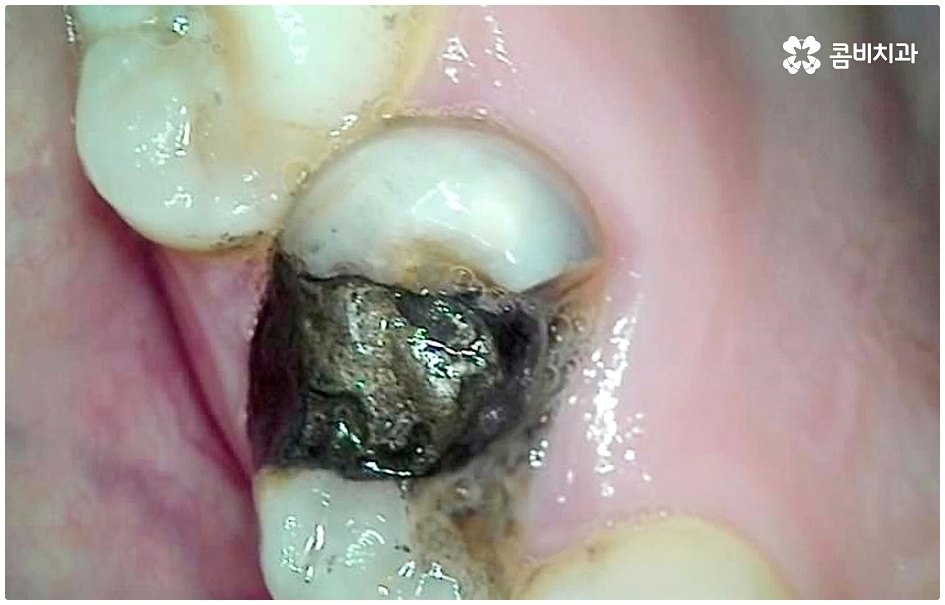

충치가 심해지면 치아가 부서지기도 하고 치수 내부까지 감염되면 극심한 동통을 일으키는 치수염으로 진행되기도 하기 때문에 그 전에 명동치과 치료를 해 주실 필요가 있어요. 충치는 하루 아침에 갑자기 상태가 나빠진다기 보다는 세균이 안쪽으로 침투하면서 손상이 단계적으로 심해지는 구강 질환이기 때문에 쑤시거나 시큰거리는 증상이 느껴지면 초기에 바로 명동치과 로 내원하셔서 검진 및 치료를 받는 것이 중요하다고 할 수 있는데요.

이 때 교합면, 즉 치아의 씹는 면이 아닌 치아 사이 충치가 생겼다면 쉽게 발견하기도 어렵고 치료를 위한 접근 역시 까다롭기 때문에 주의하실 필요가 있습니다. 물론 가장 흔하게 발생하는 것은 넓고 홈이 파여 있으며 직접 음식물을 저작하는 교합면에 생기는 충치일 것이나 음식물 찌꺼기가 끼기 쉽고 세균이 서식하기도 쉬우며 양치질을 하더라도 칫솔모가 잘 닿지 않기 때문에 관리가 어려운 치아 사이 좁은 틈새에도 역시 충치가 잘 생길 수 있는 거예요.

치아 사이 충치는 치아끼리 맞닿아 있는 부분이라 노출이 잘 되지 않기 때문에 육안으로 식별이 어려운 경우가 많은데, 만약 눈으로 확인될 정도라면 질환이 이미 많이 진행한 상태이므로 명동치과 에서 빠른 치료를 받아주실 필요가 있어요.

치아의 구조를 살펴보면 겉표면인 단단한 법랑질은 교합면에서 가장 두껍고 잇몸쪽으로 갈수록 얇아지기 때문에 치아 사이의 인접면은 치아의 신경과 한층 가까워서 충치가 조금만 진행되어도 신경치료를 받아야 할 수 있으며 인접면 충치가 심하여 레진이나 인레이 수복으로 치아의 외형을 재현하기 어려운 경우에는 치아 전체를 다듬어 씌우는 명동치과 크라운 치료를 해줘야 하니 부담이 커지기 전에 치료 시기를 놓치지 않도록 주의하시는 게 좋을 거예요.